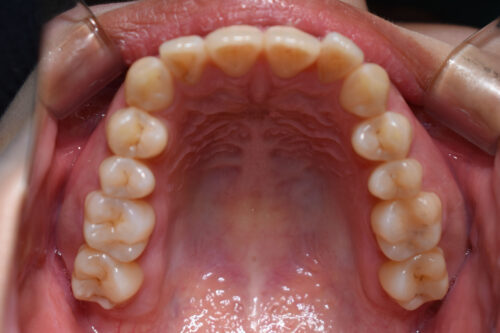

初診時年齢28歳女性

歯のがたつき(叢生)と

出っ歯

顔の長さを気になさり

巣鴨 ・ 池袋よりひとつ隣駅の東京都豊島区大塚駅すぐの大塚たまみ矯正歯科へ

来院されました。

かみ合わせは

奥歯が出っ歯方向へ

また 下方へ成長し ずれた状態で

開咬を呈しておりました。

本症例も

矯正治療の精密検査後

非抜歯矯正治療計画を立案しました。